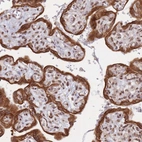

Immunohistochemical staining of human placenta shows strong positivity.